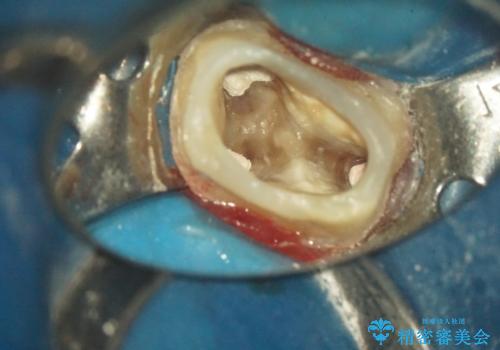

金属の奥歯 → 白い奥歯 根管治療からのやり直し

- 再根管治療→土台の築造 を行った上でのかぶせ物のやり替えをおこないました。